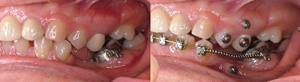

Temporary Anchorage Devices, or TADs, are miniature screws placed in your mouth that can help your orthodontist to move your teeth efficiently. Positioning the TAD is pain-free, and they are typically removed after a short period of time when they are no longer needed to assist tooth movement.

Click the image below to see examples of TADs Treatment.